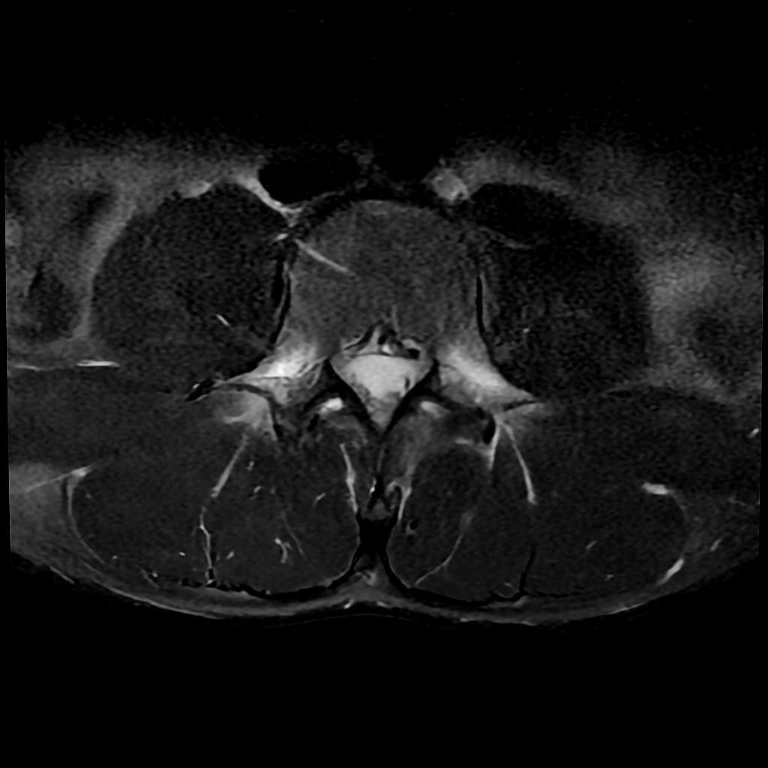

整形外科領域

脊椎

椎間板ヘルニア